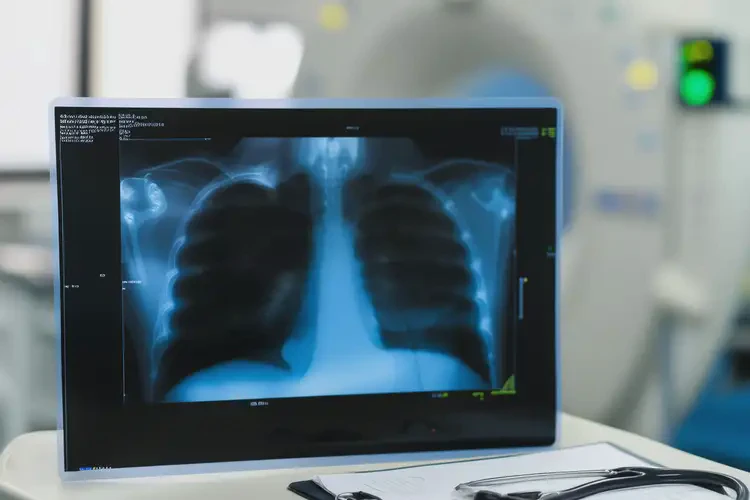

- 影像學檢查:根據需要開具X光(查看骨骼結構)、MRI(觀察軟組織、神經)或CT(精細骨結構)。

| X光片(胸椎正側位) | 150-250元 | 初步篩查骨折、脊柱側彎、骨質增生 |